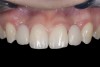

(13.) Deficient ridges in the areas of the missing lateral incisors.

Figure 13

Some patients do not want an implant due to the need for surgical intervention, and others may not have enough space for implant placement. A 15-year-old patient presented to the office after completion of orthodontic treatment to idealize the spacing of her teeth and improve her occlusal relationship (Figure 12 through Figure 14). Because both of her maxillary lateral incisors were missing, the patient was wearing a retainer with lateral incisor pontics. She had a busy school schedule, but expressed her desire for a fixed restorative option. All of her options were discussed, and the patient was informed that if she wanted an implant, she would have to wait for at least 3 to 4 years for completion of growth. The patient was not sure if or when she wanted to have an implant placed in the future, especially considering her busy schedule and desire to attend college after high school. Considering her age and the need to be conservative, a single-wing zirconia Maryland Bridge was chosen as the ideal prosthetic replacement option. Because bonding a non-etchable and smooth surface such as zirconia requires chemical adhesion, it was decided to use a modified technique to make the bridge more retentive. One of the ways to improve adhesion of a zirconia bridge is to use an etchable feldspathic ceramic layer on the internal surface of the zirconia retainer.56-58 Unfortunately, it can be difficult to determine the thickness of the ceramic and ensure accurate seating of the restoration.